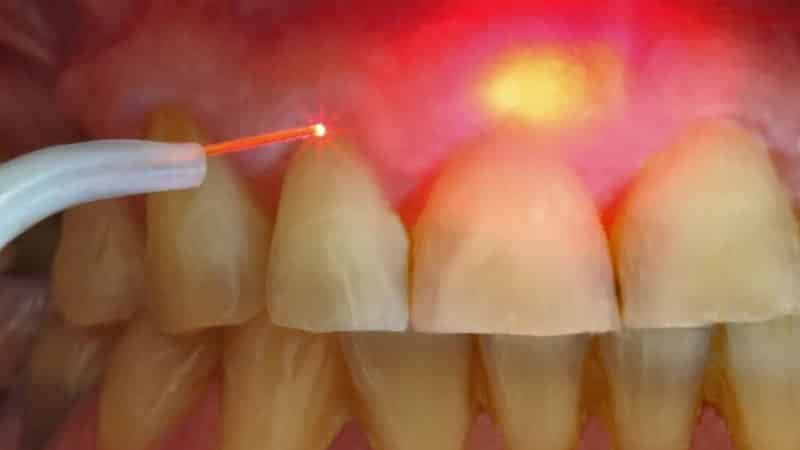

Чтобы минимизировать необходимость в хирургических процедурах, пациентам в первую очередь назначают рентгенографию и компьютерную томографию. На основе полученных данных устанавливается местоположение образования и его связь с корневой системой зуба. В процессе лечения осуществляется обработка корневых каналов с использованием специальных инструментов, лазера и медикаментов, а иногда применяется озонотерапия. После достижения положительного результата производится пломбирование.

Современным и эффективным методом на сегодняшний день является лазерное лечение.

Этот подход позволяет сохранить зуб в целостности, что является значительным преимуществом по сравнению с другими процедурами.

Лазерная технология включает несколько этапов, таких как:

- вскрытие или распломбирование зуба, расширение корневых каналов;

- введение лазера;

- уничтожение вредных микроорганизмов и удаление кисты с помощью лазерного луча.

Дезинфекция пораженных тканей, которая предотвращает осложнения и способствует быстрому заживлению, является важным преимуществом лазерного метода. Процедура, что радует пациентов, считается безболезненной и быстрой. Если через полгода после лечения киста челюсти не проявляет симптомов, дальнейшие действия не требуются, и возможно, что это была гранулема. Однако в случае длительного воспалительного процесса, который не проходит после проведенных мероприятий, пациент направляется к хирургу для полного удаления.